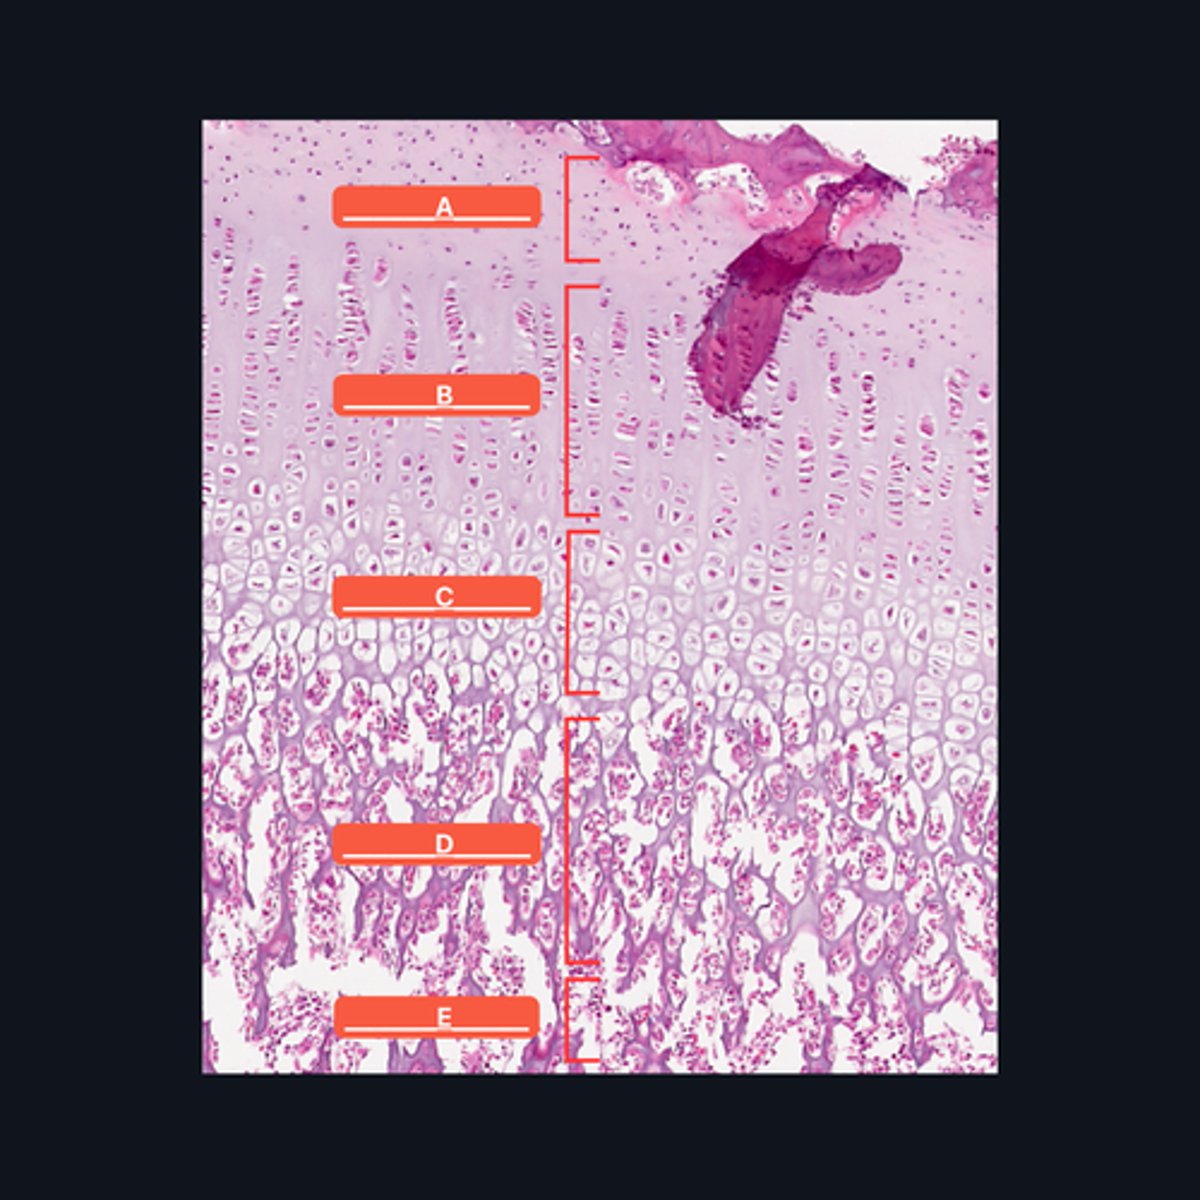

A - Zone of Resting Cartilage Cells

B - Zone of Proliferation

C - Zone of Maturation

D - Zone of Calcification

E - Zone of Ossification

Identify the pointed structures

B - Zone of Proliferation

Which pointed structure is the zone where instestitial growth occurs and what zone is it?

E - Zone of Ossification

Which pointed structure and what zone where many of the cavities left by cartilage cells merge to form marrow cavities?

C - Zone of Maturation

Which pointed structure and what zone do not divide anymore?

A - Zone of Resting Cartilage Cells

Which pointed structure and what zone anchors the epiphyseal plate to the epiphysis?

D - Zone of Calcification

Which pointed structure and what zone where the cartilage matrix is calcified